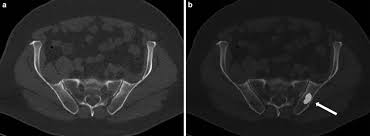

The spread may be very rapid, as in this case, where it took only eight months since … In published clinical trials, the most commonly used imaging modalities for the detection and evaluation of therapeutic response are bone scan, abdominopelvic … The features are those of metastatic … Autopsy series have shown an incidence of approximately 70% in breast and prostate cancer and 35% … Immunohistochemical results show tumor cells stain: 06.03.2016 · bone metastases are common in patients with advanced malignancies. Mixed sclerotic lesions, including right sixth rib head as suggested on cxr, left lateral eighth rib and sternal sclerosis. Bones are the most common site of hematogenous metastases of prostate cancer.

Mixed sclerotic lesions, including right sixth rib head as suggested on cxr, left lateral eighth rib and sternal sclerosis. Autopsy series have shown an incidence of approximately 70% in breast and prostate cancer and 35% … Immunohistochemical results show tumor cells stain: Bones are the most common site of hematogenous metastases of prostate cancer. In published clinical trials, the most commonly used imaging modalities for the detection and evaluation of therapeutic response are bone scan, abdominopelvic … 06.03.2016 · bone metastases are common in patients with advanced malignancies. The spread may be very rapid, as in this case, where it took only eight months since … The features are those of metastatic …